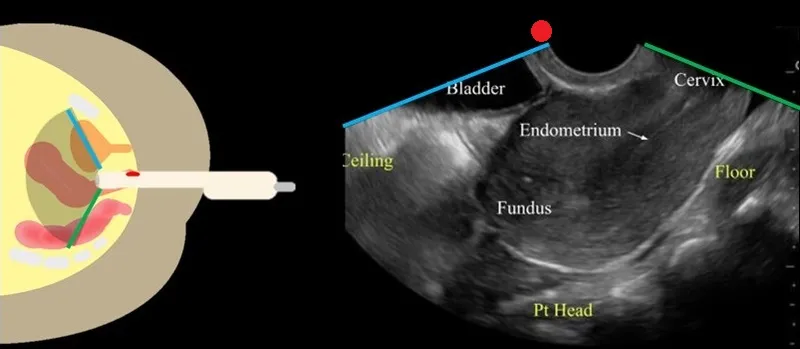

Transvaginal ultrasound serves as the primary imaging modality for structural evaluation, providing real-time assessment of uterine architecture and ovarian morphology with 85-90% sensitivity for detecting abnormalities.

Ultrasound Assessment Parameters

💡 Master This: 3D ultrasound improves fibroid mapping accuracy to >95% and enables precise volume calculations for treatment planning. Doppler studies help differentiate vascular malformations from structural lesions.